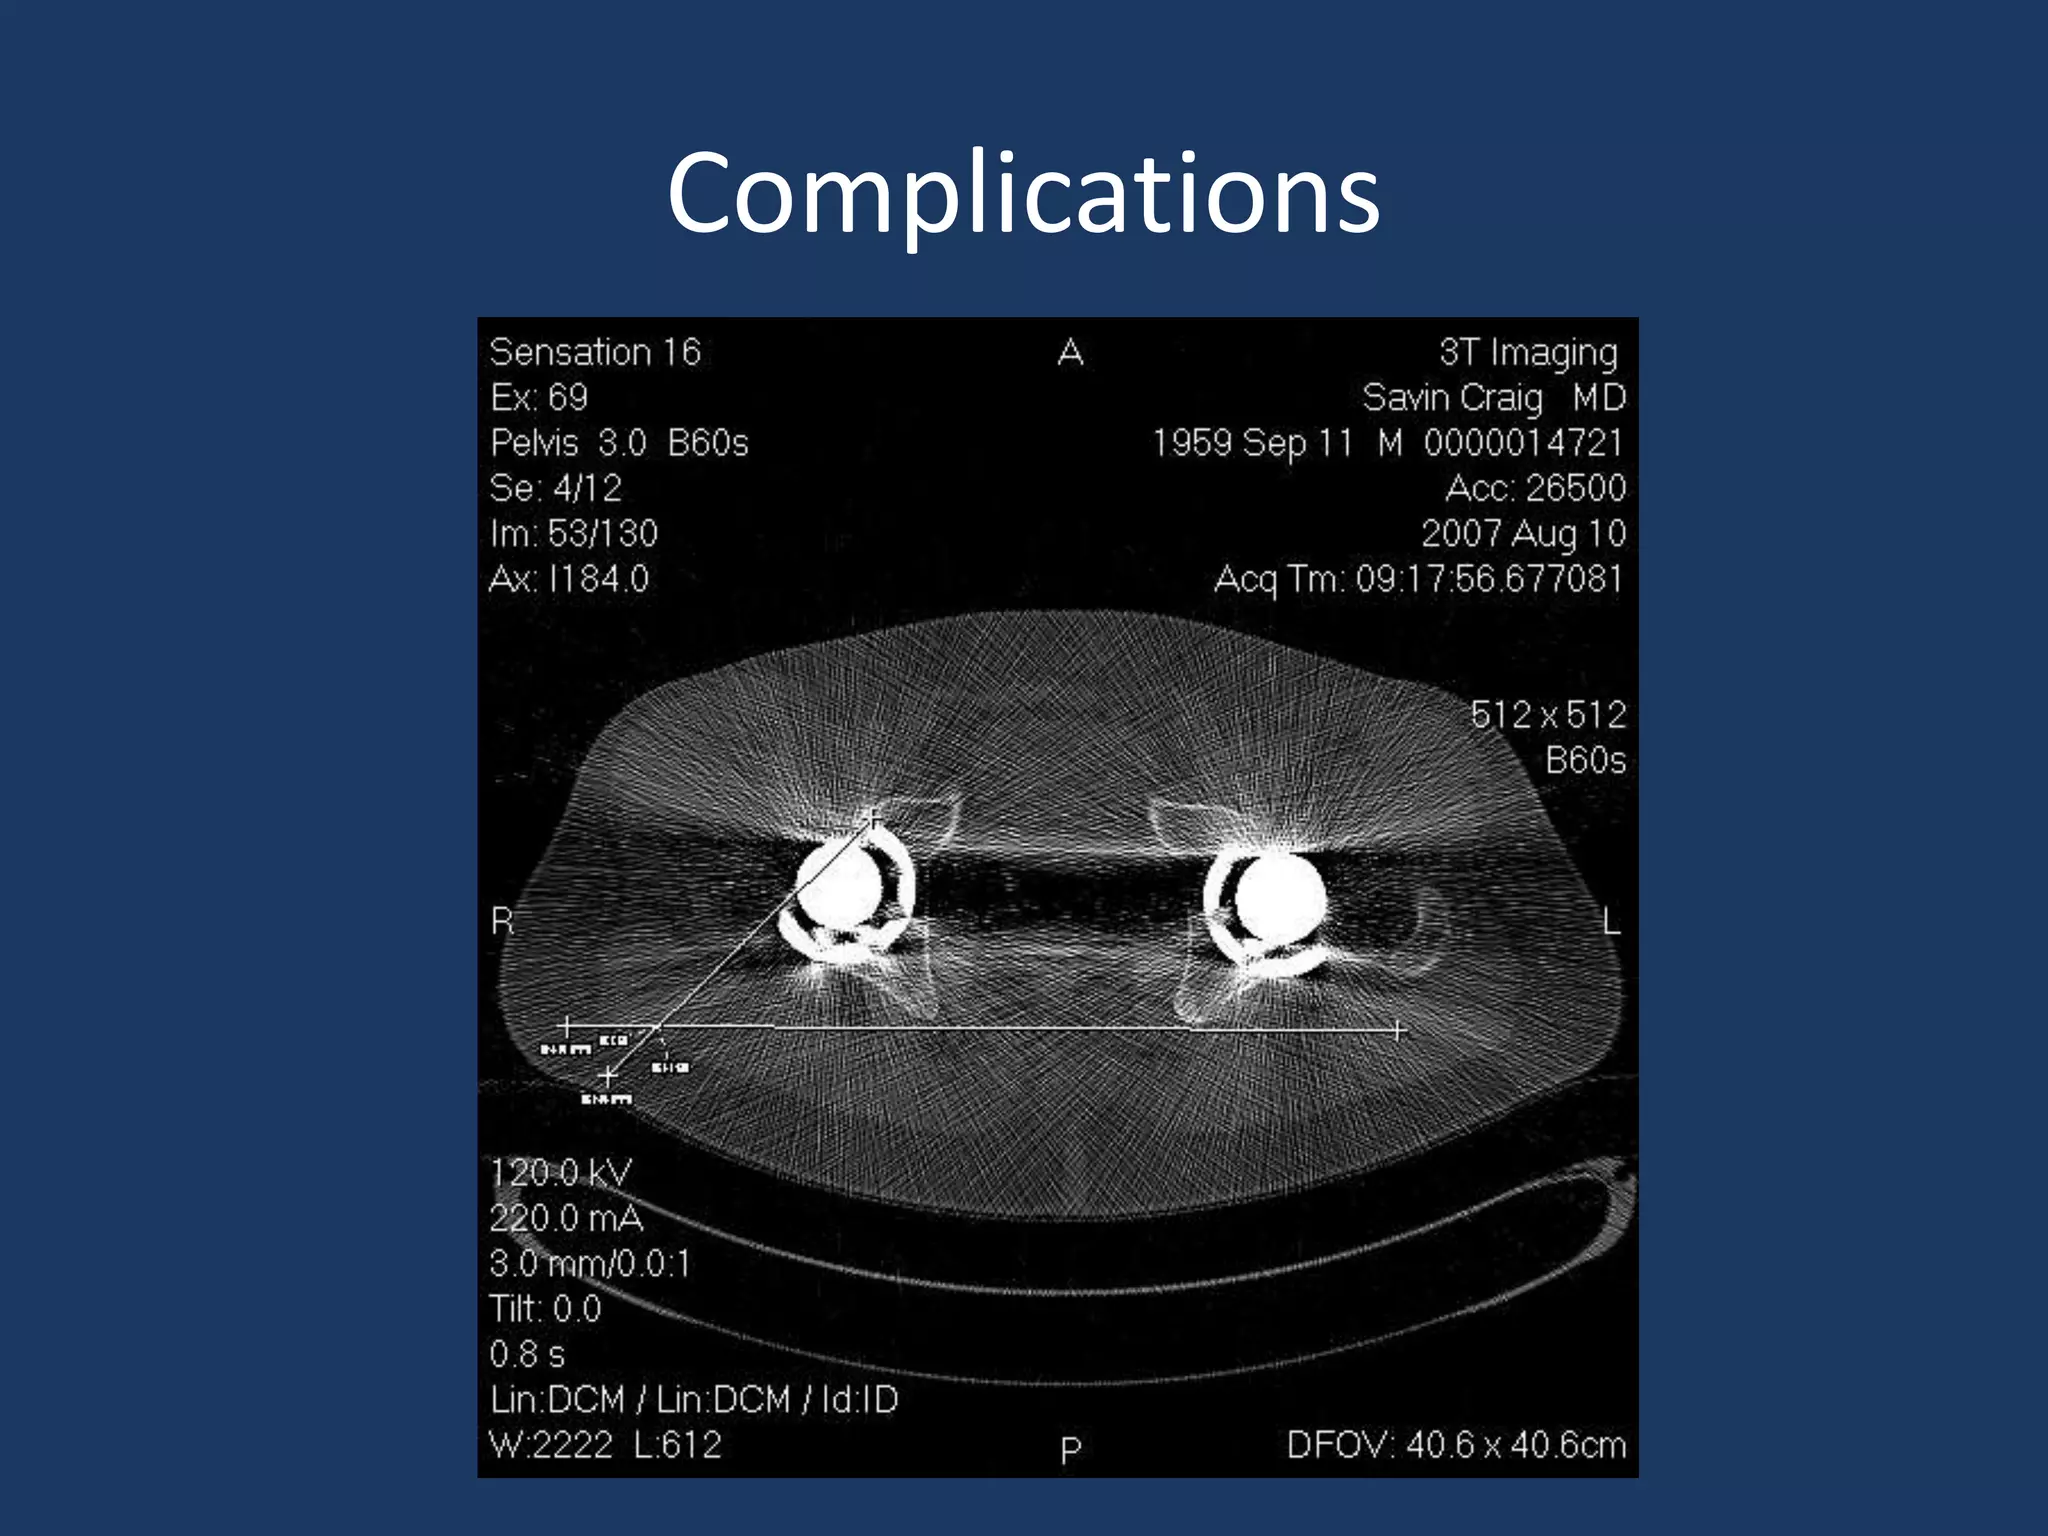

Complications

Bal BS, Haltom D, Aleto T, Barrett M. Early complications of primary total

hip replacement performed with a two incision minimally invasive

technique. J Bone Joint Surg Am. 2005

Pagnano MW, Leone J, Lewallen DG, Hanssen AD. Two-incision THA

had modest outcomes and some substantial complications.

ClinOrthopRelat Res. 2005

Pagnano MW, Trousdale RT, Meneghini RM, Hanssen AD. Slower

recovery after two-incision than mini-posterior-incision total hip

arthroplasty: surgical technique. J Bone Joint Surg Am. 2009